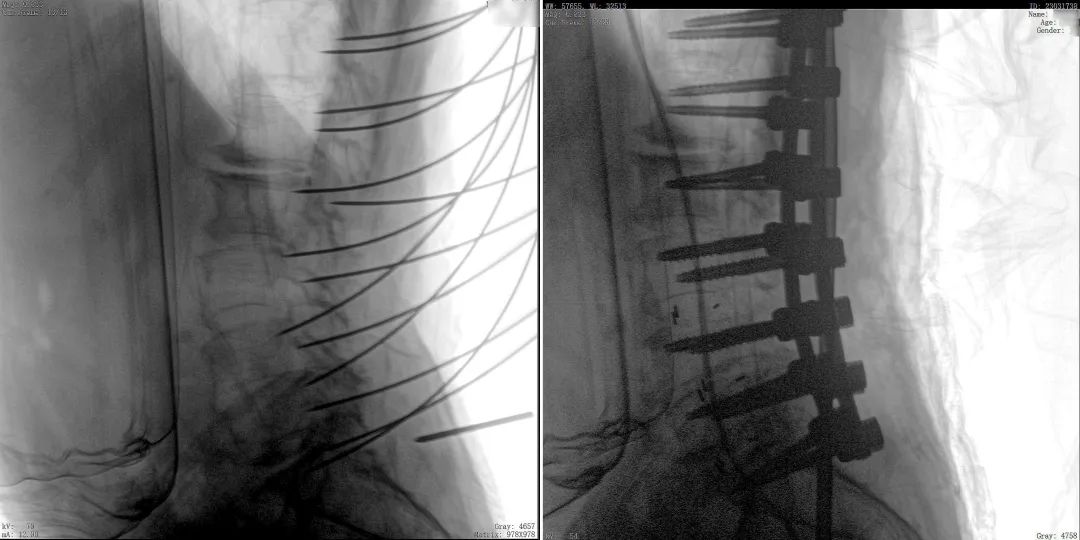

Robot-Guided Needle Insertion After establishing the surgical approach, the mechanical arm maintained a stable trajectory, allowing the surgeon to focus solely on drilling and screw placement. The needle insertion was notably stable, with sub-millimeter precision. Images: [Insert images] In contrast to traditional surgery, which requires repeated needle insertions, this robot-guided approach ensures precision and reproducibility, minimizing individual variations and reliance on the surgeon's experience.

Ensuring a Smooth Surgical Experience The C-arm verified the accuracy of the needle path, simulating the ideal screw size based on the navigation plan and ensuring the correct placement of all 14 screws within the vertebral arch, as designed preoperatively.